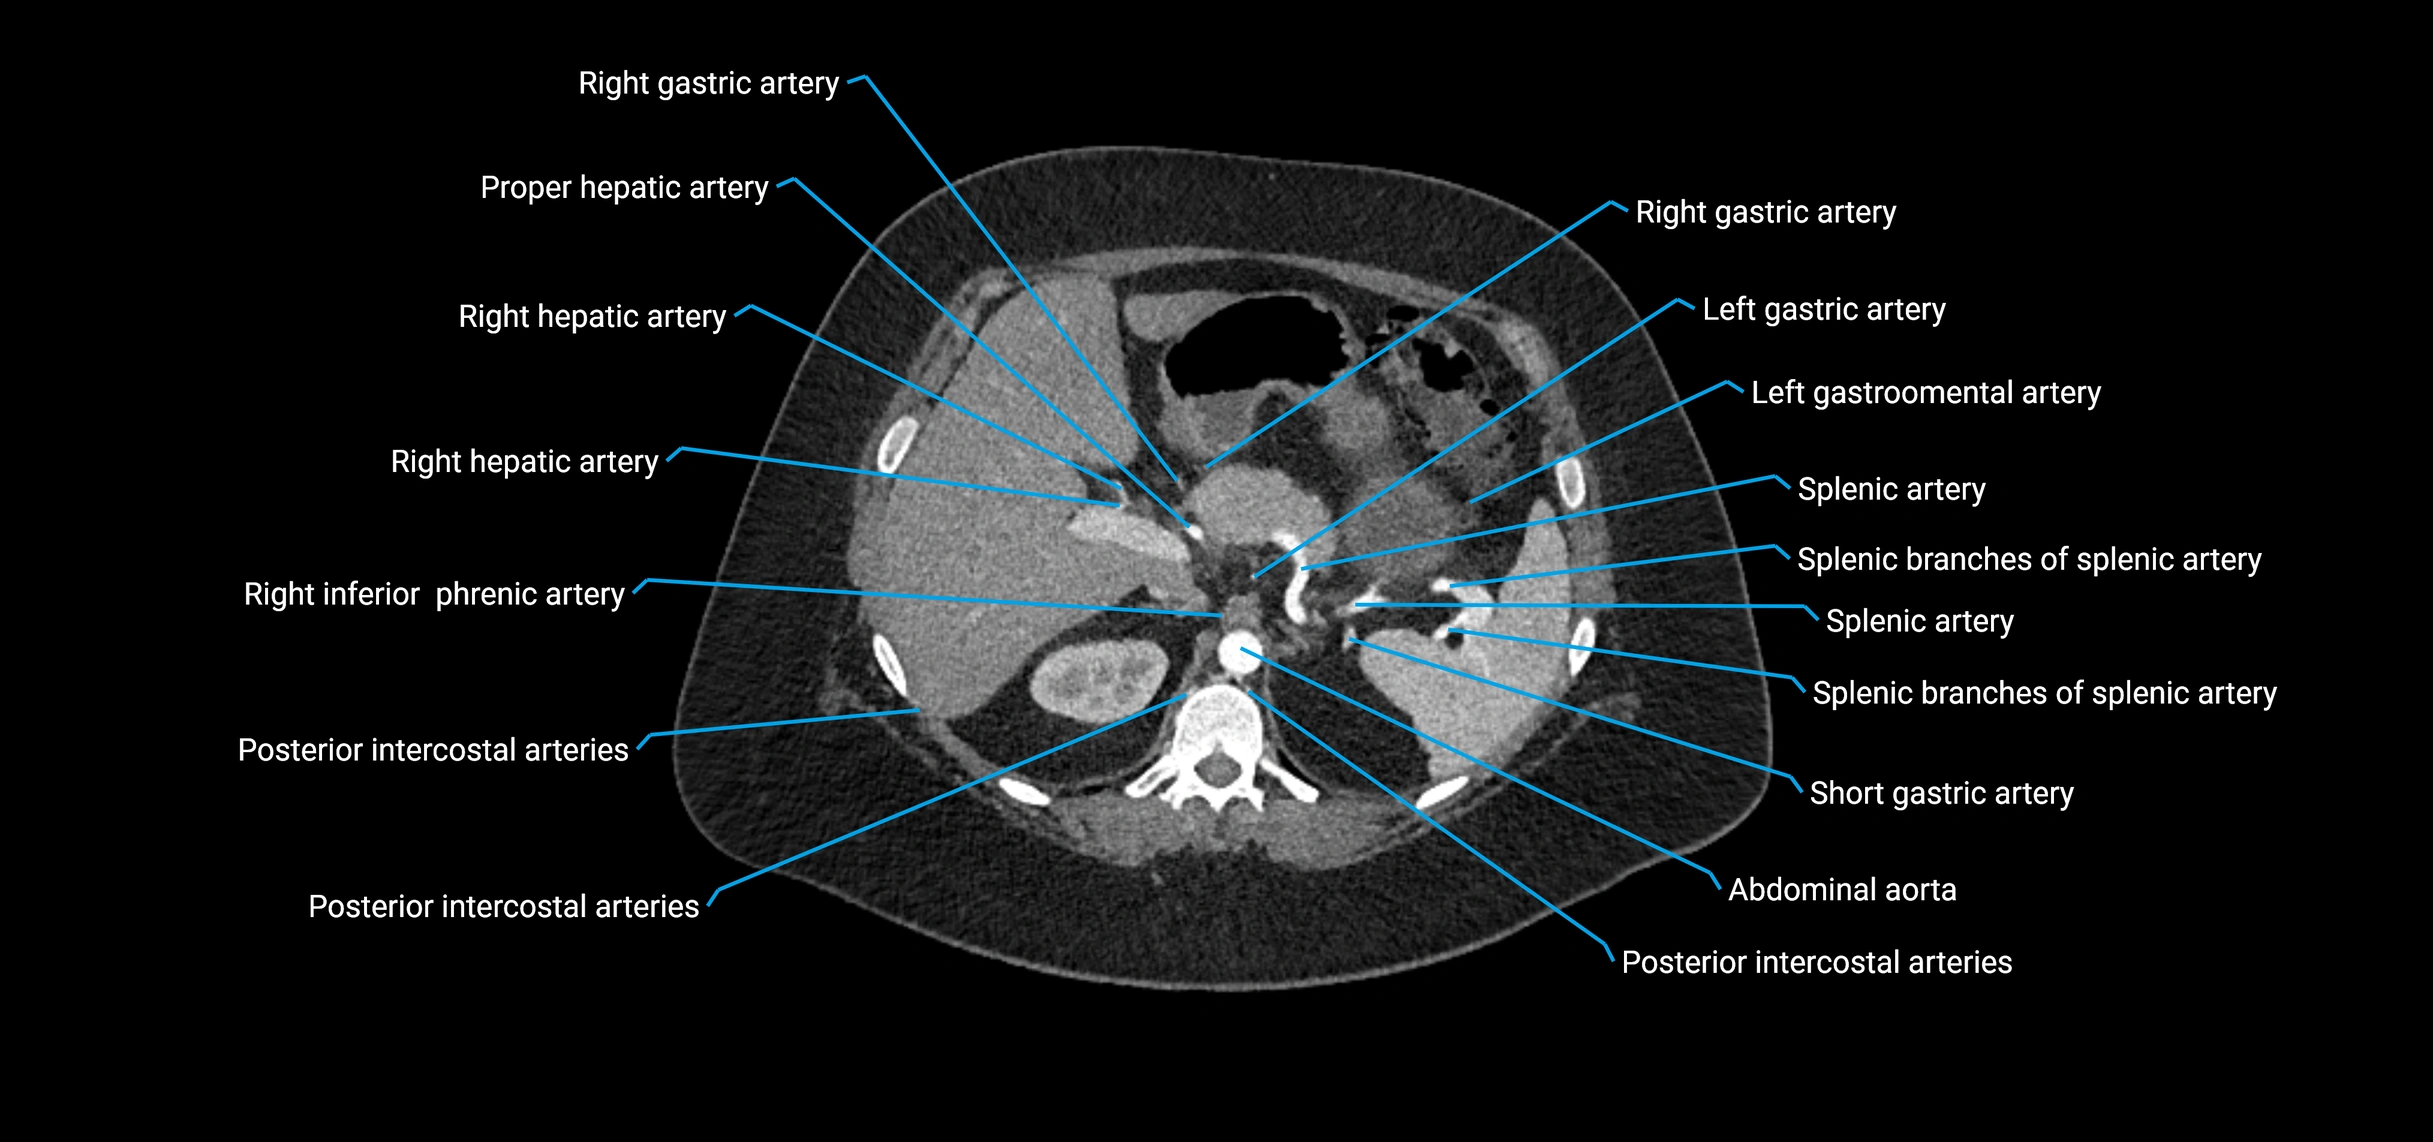

Contrast-enhanced CT (CTA):

• Gold standard for abdominal aortic imaging

• Provides excellent detail of lumen, wall, aneurysm, thrombus, and branch vessels

• Multiplanar and 3D reconstructions help in aneurysm measurement, stent graft planning, and dissection evaluation

• Detects acute rupture, traumatic injury, or occlusion with high sensitivity